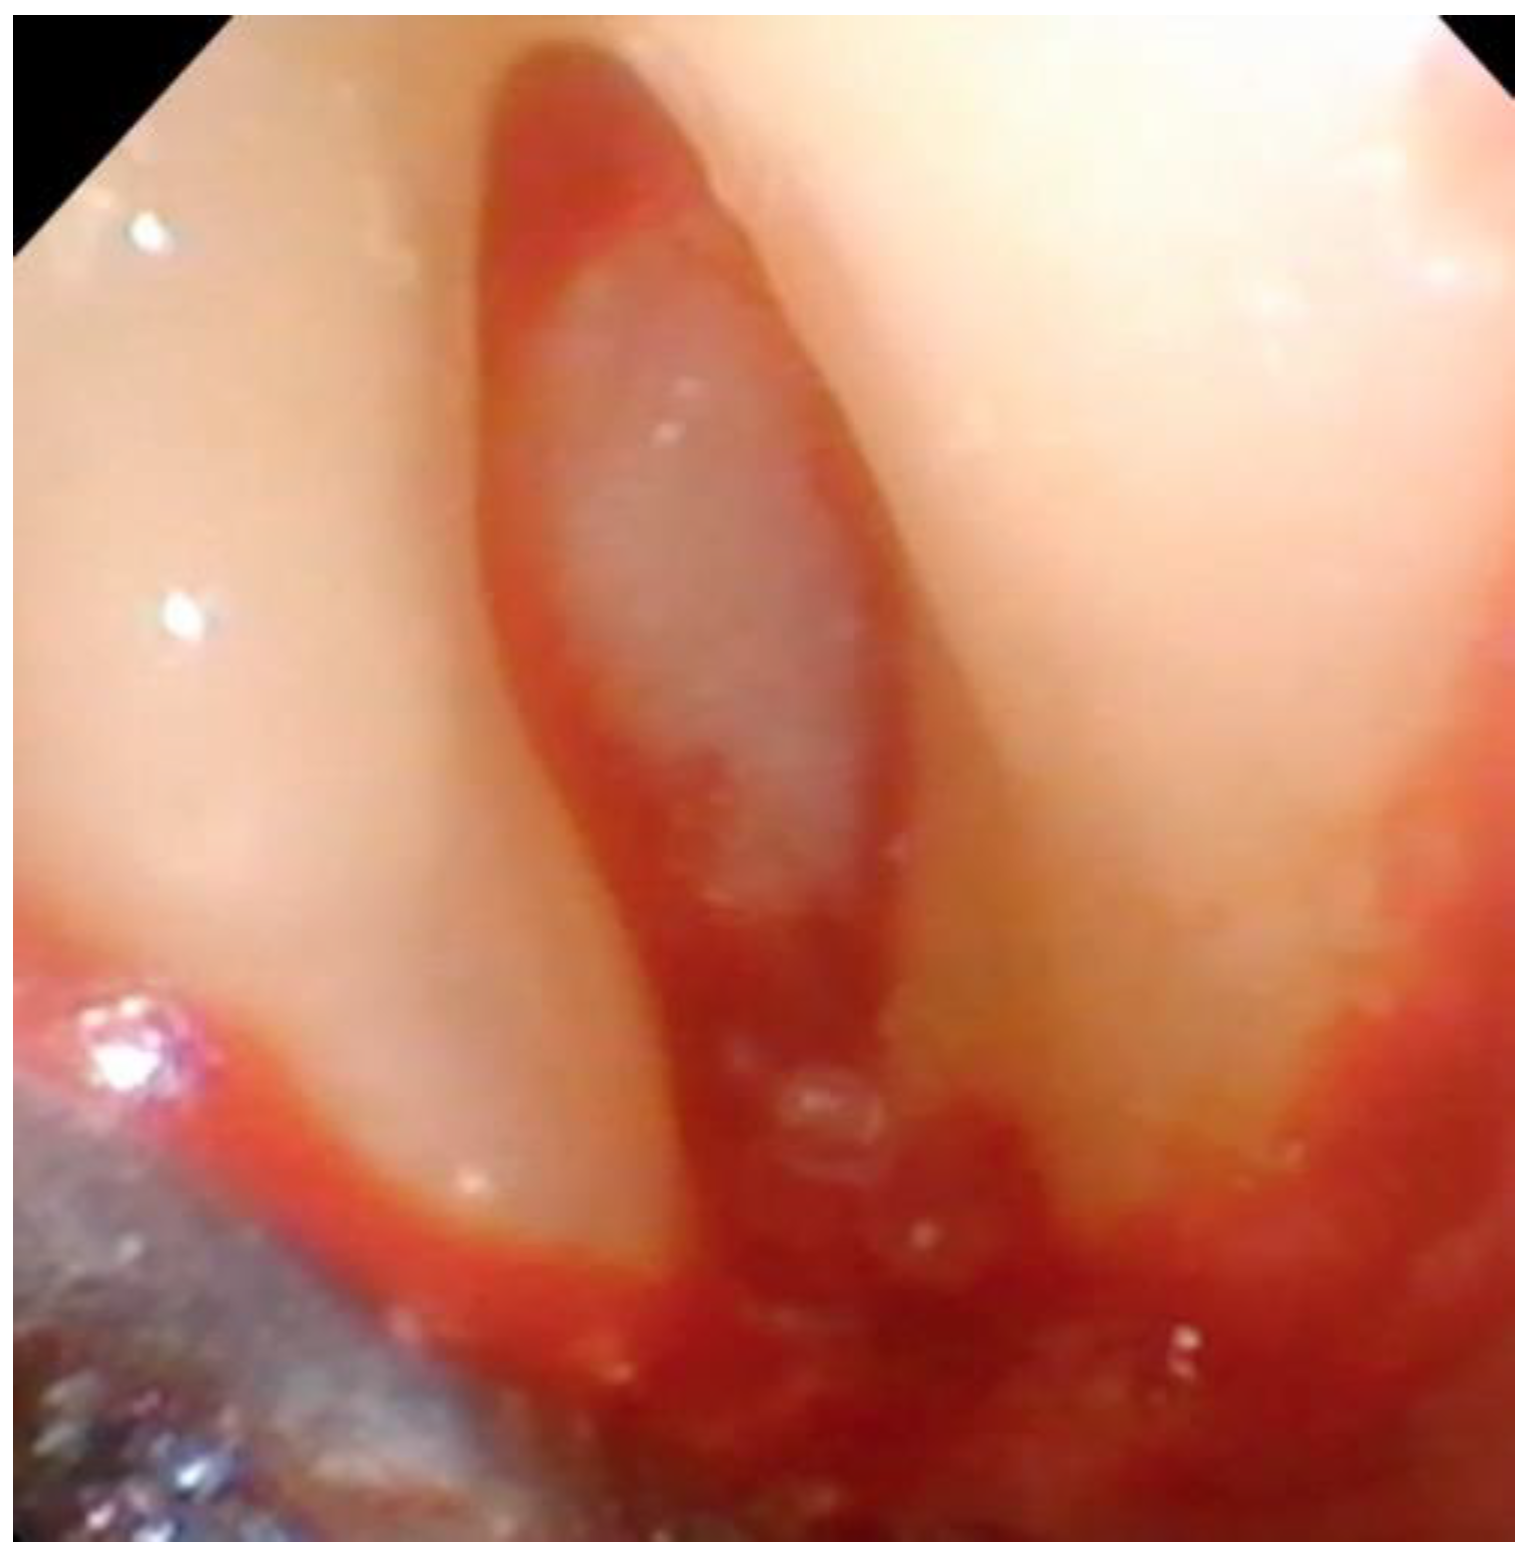

Debridement—Once incisions and the small split-thickness lingual flap have been made, the retractor on the handpiece of the videoscope is inserted, and light pressure is placed on the flap so that the defect can be visualized. Generally, there will be a significant amount of granulation tissue in the defect which must be removed. This is usually performed with a Younger-Goode curette that has been reduced in size by about one-third from its original size. This curette is used in an action similar to using an instrument to “spoon” out caries from a tooth. This action is more suitable for the small flaps of VMIS than the traditional “scaling” action used with surgical curettes. Once the granulation tissue has been removed, the root surfaces can be debrided of accretions and roughness. This is performed with a combination of ultrasonic instrumentation and hand instruments. The videoscope is used throughout the debridement process. When an ultrasonic scaler is used, there will be some transient blurring of the videoscope image due to water on the lens, but the air over the lens clears the image in a matter of seconds when the ultrasonic scaler is turned off. After mechanical debridement of the roots, they are dried with gauze and thoroughly inspected with the videoscope. The 20 to 40× magnification of the videoscope often reveals “micro-islands” of calculus and anatomical roughness on the root surface. 20 These can be removed with the use of EDTA (Prefgel, Straumann, USA), recommended by the manufacturer for the biomodification of the root surface before using EMD. A fully debrided defect ready for bone grafting is shown in Figure 4.

Figure 4. A furcation defect that has been fully debrided and EDTA used to remove any micro-islands of calculus. This site is ready for bone grafting and enamel matrix derivative (EMD) treatment.